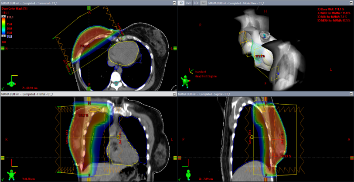

Posterior a la cirugía, se administra RT con técnica conformada con planificación 3D (RTC3D). A todas las pacientes se les realizó tomografía computarizada (TC) de tórax con o sin contraste en inmovilizador de mama; se delimitaron los volúmenes blancos: glándula mamaria y lecho o pared costal, fosa supraclavicular (FSC) según fuera el caso y los órganos a riesgo (OAR): pulmones, corazón, médula espinal y esófago, en cada una de las pacientes. Para la planificación del tratamiento radiante posterior a cirugía preservadora, el volumen tumoral clínico (CTV) incluye toda la glándula mamaria, la cual se delimita mediante marcadores fiduciarios. El volumen de planificación (PTV) incluye el CTV más un margen de 2 cm en sentido cráneo caudal. En las pacientes posmastectomía el CTV incluye la pared costal y/o FSC y el PTV es el CTV más margen para corregir las incertidumbres del posicionamiento. Se emplearon campos tangenciales para el tratamiento de la mama/pared costal y campo directo para la FSC, los cuales se conforman a través del colimador multiláminas para disminuir la irradiación de los OAR (pulmón y corazón) (Figura 1 y 2). Por medio de histogramas dosis-volumen se evalúa la dosimetría, a nivel los volúmenes descritos. Las pacientes fueron tratadas en su mayoría en posición supina con uso de soporte de mama y en algunos casos de mamas péndulas y voluminosas se utilizó la posición prona, en un soporte en el cual la mama a tratar queda suspendida.